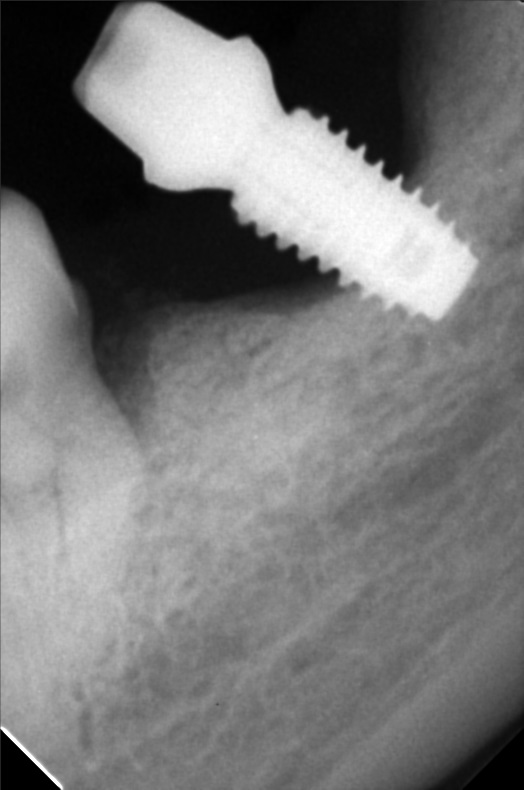

- Procedure